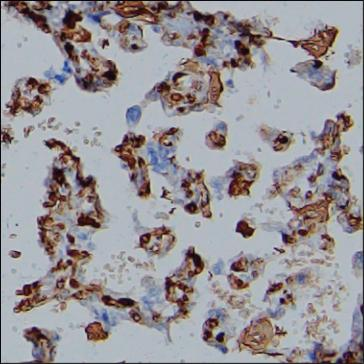

| IHC | 1/500 | Human,Mouse,Rat |